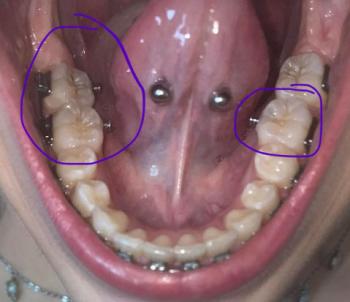

The image shows an area near the lower back teeth where the gum tissue appears thin or missing, exposing the underlying soft tissue. The marked area (“no skin”) suggests loss of normal gum coverage, which can make the area sensitive, sore, and vulnerable to infection.

The nearby teeth appear intact, but the gum condition indicates localized tissue damage or recession.

This case shows loss of protective gum tissue near a lower molar, making the area vulnerable. Early dental evaluation is important to prevent infection, protect bone, and restore comfort.